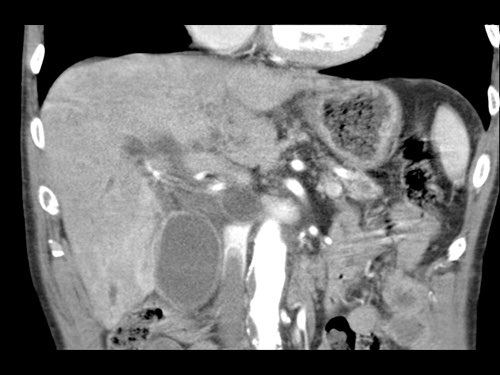

Việc sử dụng tái tạo đa mặt phẳng (multiplanar reformation) giúp cải thiện hiệu quả chẩn đoán tổng thể của CT, như được minh họa trong trường hợp này.

Tái tạo mặt phẳng coronal cho thấy một khối u nhỏ ở đầu tụy (đầu mũi tên) gây tắc nghẽn ống mật chủ.

Có vẻ chỉ có tiếp xúc hạn chế với tĩnh mạch cửa (mũi tên).

Tiếp tục xem các hình ảnh tiếp theo.

Tái tạo đa mặt phẳng vuông góc với tĩnh mạch cửa cho thấy mức độ tiếp xúc với tĩnh mạch cửa rộng hơn, từ 90 đến 180 độ (mũi tên).

Khi không có bất thường bờ viền, trường hợp này được phân loại là có thể cắt bỏ giới hạn (borderline resectable) theo tiêu chí DPCG, nhưng có thể cắt bỏ (resectable) theo tiêu chí NCCN.

Phẫu thuật cắt bỏ không kèm tái tạo tĩnh mạch cho kết quả R1, tức là có xâm lấn vi thể của khối u tại diện cắt.